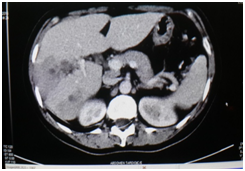

Male patient of 37years of age , white race, resident in Habana del Este municipality of Havana province, with previous health history that comes to consultation for presenting prolonged febrile syndrome with 56days of evolution, febrile peaks of 38‒39 degrees, accompanied by chills and decay. Urinary sepsis was determined as initial diagnosis so antimicrobial treatment was imposed for 10 days. There is no improvement in the clinical picture and the febrile symptoms persist. The patient is admitted to the hospital service of the Central Hospital in Havana. On physical examination, painful abdomen on palpation in the right hypochondrium and epigastrium without other alterations Laboratory tests are performed or presenting Haemoglobin: 12gl, Leucogram which yields an Eosonophilia of 66% and an Erythrosedimentation: 67. Serial blood cultures and urine cultures they were negative. Likewise, the serology was negative. Within imaging studies abdominal ultrasound reporting hepatomegaly that exceeds be 2 cm costal margin with the presence of a hypo echoic image with nodular, peripheral tendency without flow Doppler level right lobe study (Figure 1) interpreting c indicated omo pyogenic liver abscess therefore imposes treatment with antimicrobial therapy (Metronidazol EV) (Figure 1). Ultrasound: nodular, hypoechoechoic, peripheral, non‒vascularised image at the level of the right lobe of the liver clinically the patient improved his general condition, but he kept the febrile syndrome accompanied by diffuse abdominal pain. By keeping the same ultrasound image last month of treatment study it was conducted by T omografía who reported abdominal the presence of density areas of irregular appearance, in the right lobe of the liver in segments VII and VIII and endovenous study showed lesions with poor contrast capitation both Portal and late phase (Figure 2). Computed tomography with intravenous contrast: hypo dense areas of irregular appearance at the level of segments VII and VIII of the liver with poor contrast uptake Ultrasound images suggested the diagnosis of parasitosis Fasciola hepatica but also by positron raised the differential diagnosis of Focal nodular hyperplasia at que sugi river echo directed FNA that reported cytological Negative of neoplastic cells and inflammatory infiltrate with abundant eosinophils. Given this possible diagnosis, endoscopy was performed, which reported alkaline pangastropathy with a duodenal swab for negative parasitological study. Conical crown was made on several occasions resulting negative and biliary drainage was indicated to be not useful for diagnosis. In view of Clinical and Imaging suspicion of Fasciola hepatica, it was decided to perform a weekly evaluative ultrasound for 4 more weeks, observing at the end of the fourth week echogenic images, elongated with movements inside the gallbladder and an echogenic image without acoustic shadow in the canal. Coledochus suggesting the diagnostic imaging of adult Fasciola parasites in the bile ducts (Figure 3). Evolutionary ultrasound: echogenic images, free, with movement at the level of the gallbladder. The patient was referred to the Institute of Tropical Medicine (IPK) where the diagnosis was verified, imposing treatment with a single oral dose of Triclabendazole with excellent therapeutic response.

Figure 3 Evolutionary ultrasound.

In hepatic fascioliasis, hypo echoic, anfractuous, well‒defined focal lesions of variable size can be observed, with a tendency to accentuate in 96% of cases (similar to the case reported), although variable echo genicity is also described . However, it is not always possible to visualize the paths that give it the characteristic stamp, so its role in acute Fasciolosis is less. The presence of per portal adenopathies is also described in 74% of cases, although this finding is nonspecific and is present in acute and chronic hepatitis, abdominal neoplasm’s, abdominal tuberculosis and sclerosing cholangitis, among other pathologies.13,14 In Biliary Fascioliasis, the role of ultrasound is greater, given that it is able to confirm parietal thickening of the common bile duct with moderate dilation , although this finding is also seen in pathologies such as sclerosing cholangitis and AIDS cholangitis . More specific is the observation of mobile structures in the gallbladder and / or common bile duct, representing the adult form of Fasciola,14,15 a finding found in the reference patient.